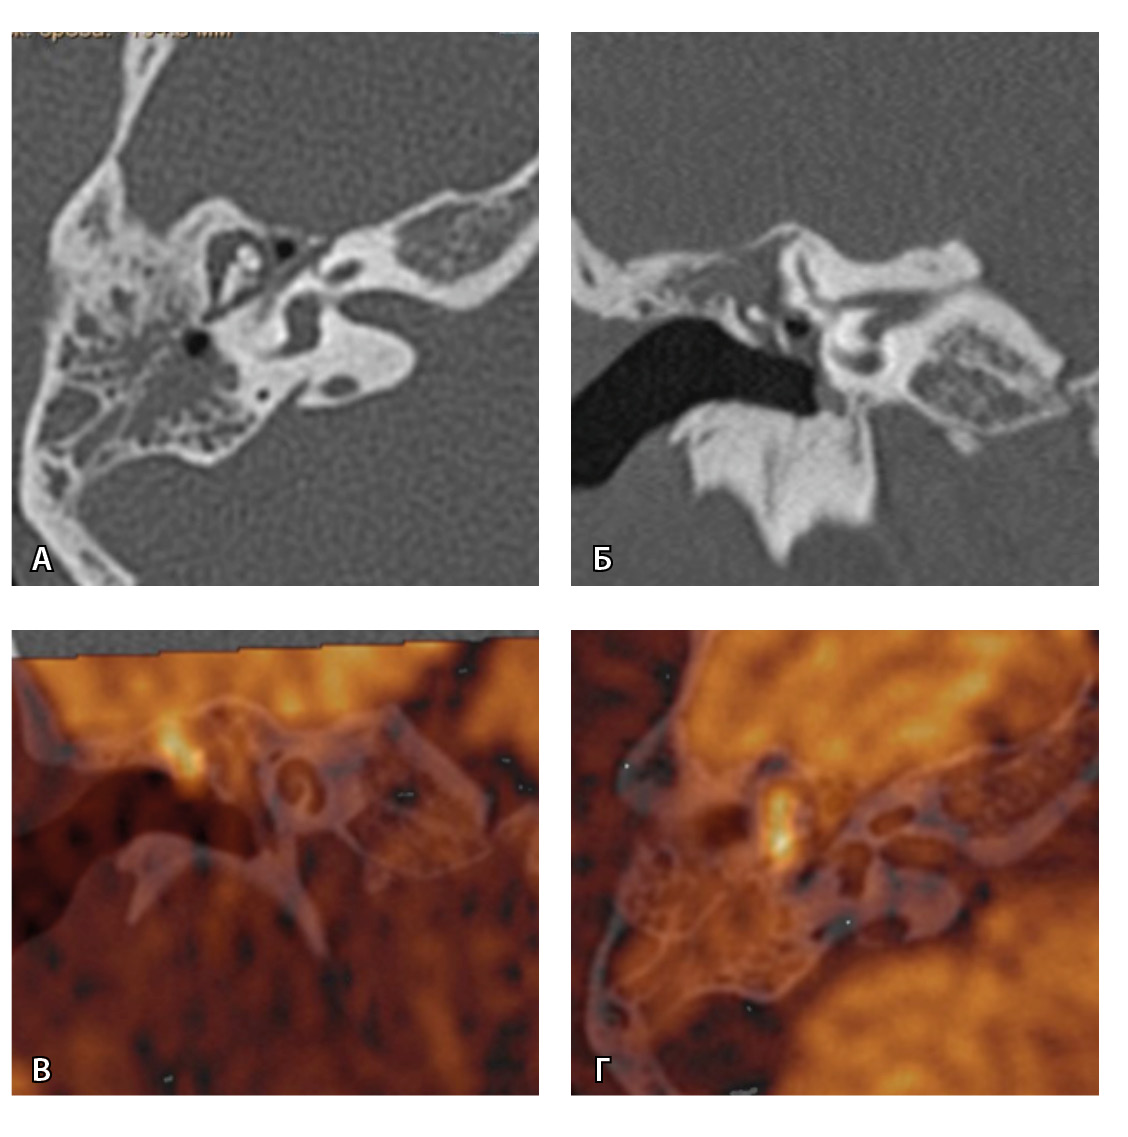

Для слияния изображений выбирались пациенты, у которых были выполнены обе модальности – КТ и МРТ – и только те исследования, где при МРТ определялось ограничение диффузии и его локализация могла соответствовать холестеатоме – впервые выявленной или рецидивной. Были совмещены 236 пар исследований ушей (КТ и МРТ) с МР-картиной высокого МР-сигнала при диффузии (рис. 2).

На рис. 3 и 4 показано расхождение данных КТ и МРТ.

Рис. 3. Хронический правосторонний средний отит. По данным компьютерной томографии (А, Б) нет ремоделирования барабанной полости, деструкции и смещения косточек, скутум сохранен, данных за холестеатому нет. При магнитно-резонансной томографии (В, Г) у того же пациента выявлен очаг высокого магнитно-резонансного сигнала, который при слиянии локализовался в области пространства Пруссака. Заключение и интраоперационно – холестеатома пространства Пруссака

Рис. 4. При компьютерной томографии (КТ) визуализируются признаки хронического гнойного среднего отита справа. Наблюдаются латерализация косточек среднего уха и узурация их по имедиальной поверхности на уровне эпитимпанума (тело наковальни и головка молоточка) – классические КТ-признаки холестеатомы натянутой части барабанной перепонки (А, Б). Однако по данным магнитно-резонансной томографии (В) и в последующем при оперативном лечении холестеатома не подтверждена